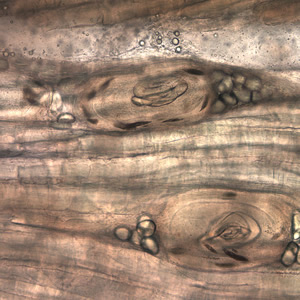

Case #199 – March, 2007

A huntsman killed a bear and prepared it for eating and freezing by cutting it into roasts, steaks, and grinding the trimmings. Later that same day, he ate a burger made from some of the fresh meat and cooked rare. Approximately two and a half to three weeks later, the hunter experienced fever, diarrhea, and muscle pain. However, medical attention was not sought for another six weeks. He had elevated eosinophilia and several laboratory tests were ordered. The Division of Parasitic Diseases’ reference diagnostic laboratory received some of the bear meat for examination. A digestion technique using 0.1% pepsin and 0.1% hydrochloric acid was used on the meat and a muscle squash was made from the softened tissue. Figure A, taken at 400× magnification, and Figures B-E, taken at 1000× magnification, show what was observed. What is your identification of the objects in the meat? What is your diagnosis? Based on what criteria?

Figure B

Figure C

Figure D

Figure E